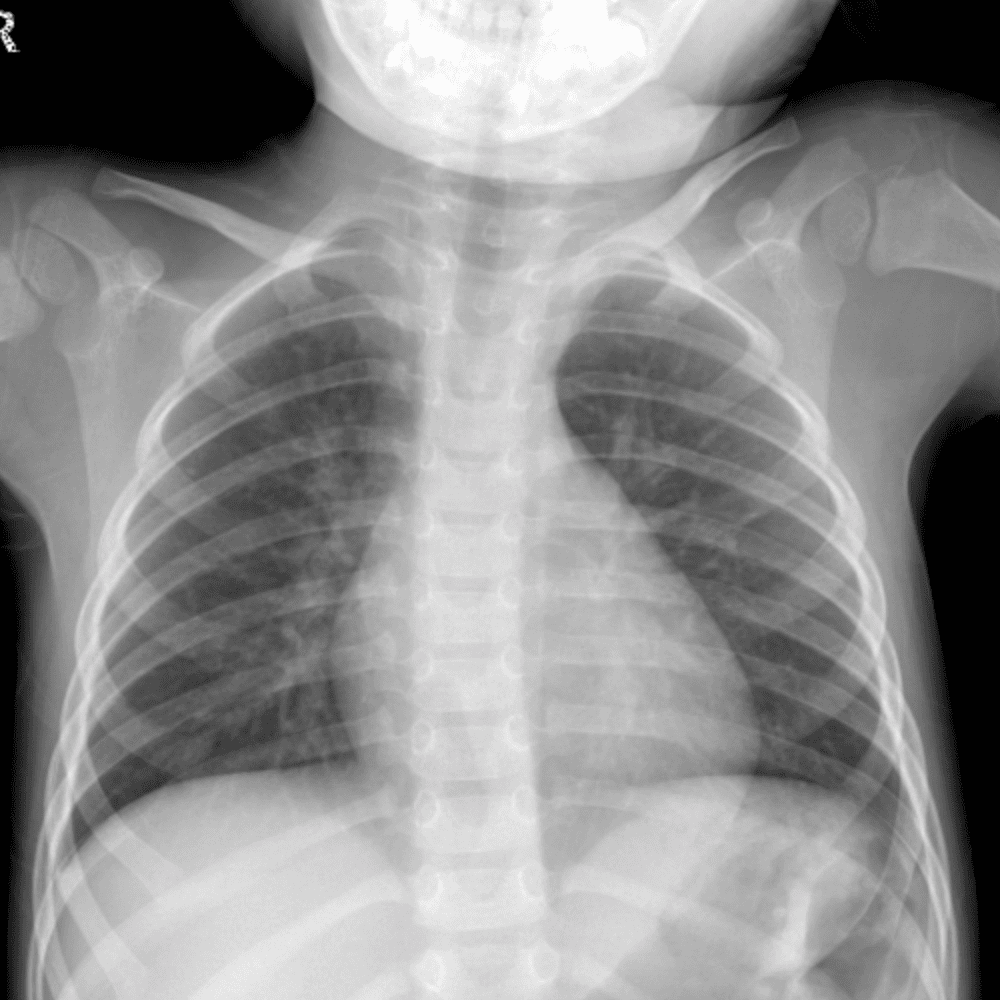

Peds Chest

Practice

Simulates call by including subtle or difficult cases and some normals.

50 cases